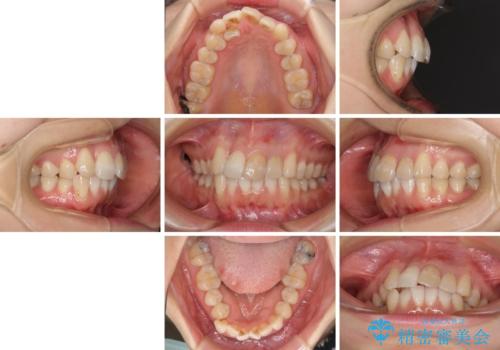

内側にある歯が邪魔 重なった前歯の歯列矯正

- 重なった前歯を邪魔に感じ、汚れも溜まりやすいことを気にして来院された患者様です。

右上前から2番目の歯が内側に転位しているため、上顎の正中は右にずれていました。

内側に転位していた歯はきれいに歯列に収まり、清掃性が著しく改善しました。

元々神経の失活してしまっている前歯2本は変色が目立つようになってきたため、今後セラミッククラウンによる補綴治療を行う予定です。